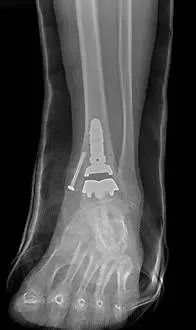

The following are images after surgical replacement of the ankle joint with a mobile bearing ankle prosthetic called the S.T.A.R. (SBI). This replacement joint will function similarly to a normal anatomical joint, allowing the patient normal function in daily activities, but was not designed to take repetitive use during more intense athletic activity. The joint has a polyethylene spacer between two metal parts that acts as shock absorber and gliding agent similar to cartilage. There is physical therapy that is required after surgical joint replacement in order to get the patient back to funcional capacity.

These are final pics of the ankle replacement after fusion takedown

Pre and Post op Pics of Arthiitic Ankle S/P Total Ankle Replacement (TAR)

Preop, Intraop and Postop X-rays status post Total Ankle Replacement for Ankle Arthritis